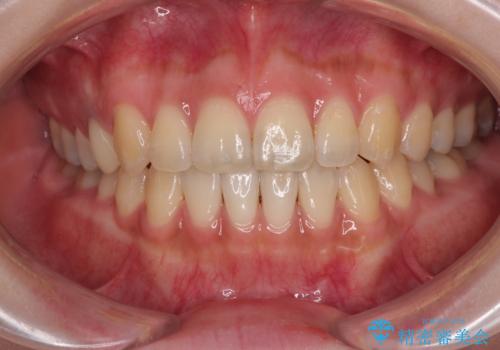

顎が左右にずれた咬み合わせ ハーフリンガルの抜歯矯正

裏側装置での交叉咬合改善は非常に困難なもので、頻繁に装置の脱落がありました。

それでも想定以上に治療期間は長期化せず、咬み合わせも口元も満足のいく仕上がりとなりました。